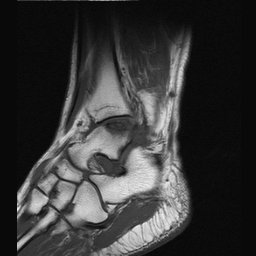

Return to Osteochondritis Dissecans